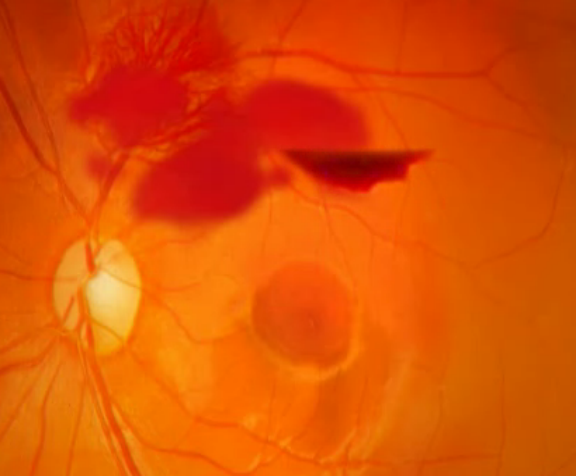

MEDICAL RETINA

Paras Netralaya offers comprehensive retina surgeries and treatments, including angiography and LASER procedures. Trust us for all your retina care needs, ensuring expert solutions and advanced treatments for optimal eye health.

Medical Retina Services

Diabetic Retinopathy Treatment, Diabetic macular edema treatment, Lasers, Green laser, Intravitreal Injections.